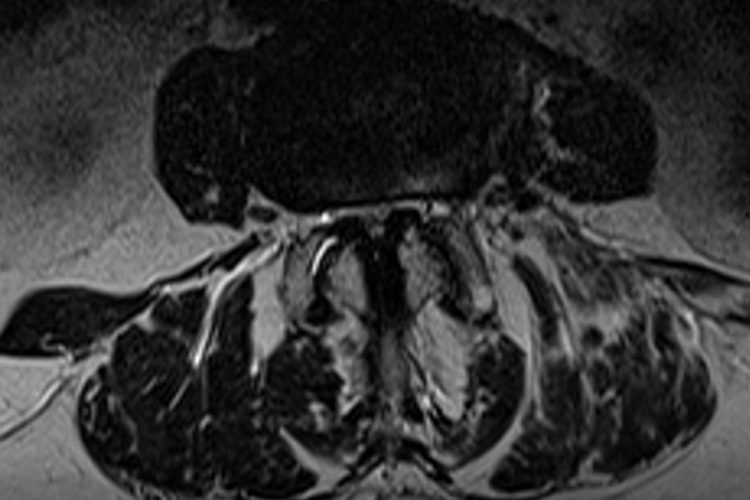

11.06.2019 – Prof. Ohnsorge zur Visite im NDR Am 11.06.2019 war Prof. PD Dr. Jörg Ohnsorge als Experte in der Fernsehsendung „Die Visite“ im NDR zum Thema Iliosakralgelenk (kurz ISG) zu Gast. Zuerst wurde im Beitrag über verschiedene Ursachen und die Wirkungsweise einer Blockade im ISG / Iliosakralgelenk oder Kreuz-Darmbein-Gelenk (Umgangssprachlich für das ISG)…